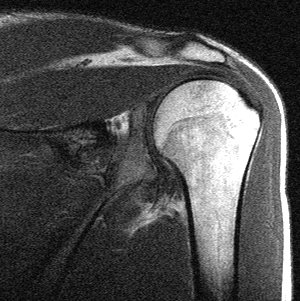

Bild 2: Schulter von hinten.

Die Muskelgruppe, die der Schulter diese Flexibilität ermöglicht nennt man die Rotatorenmanschette. Vier Muskeln greifen wie die Finger einer Hand um den Oberarmkopf der Schulter und stabilisieren ihn mit ihren Zügen die Bewegungen und halten damit den Schultergelenkkopf in der Schulterpfanne. In der nebenstehenden Kernspintomografie sehen wir ein Schultergelenk von hinten. Hell auf der rechten Seite sehen wir den Oberarmkopf, darüber ebenfalls hell, das Schulterdach, aus Acromion und Schlüsselbein mit dem Schultereckgelenk. Sehr klein links neben dem Oberarmkopf ist dunkler die kleine Gelenkpfanne der Schulter zu erkennen. Der große spindelförmige Muskel zwischen Schulterdach und Schultergelenk ist einer der sog. Rotatoren mit dem klangvollen Namen Musculus supraspinatus.